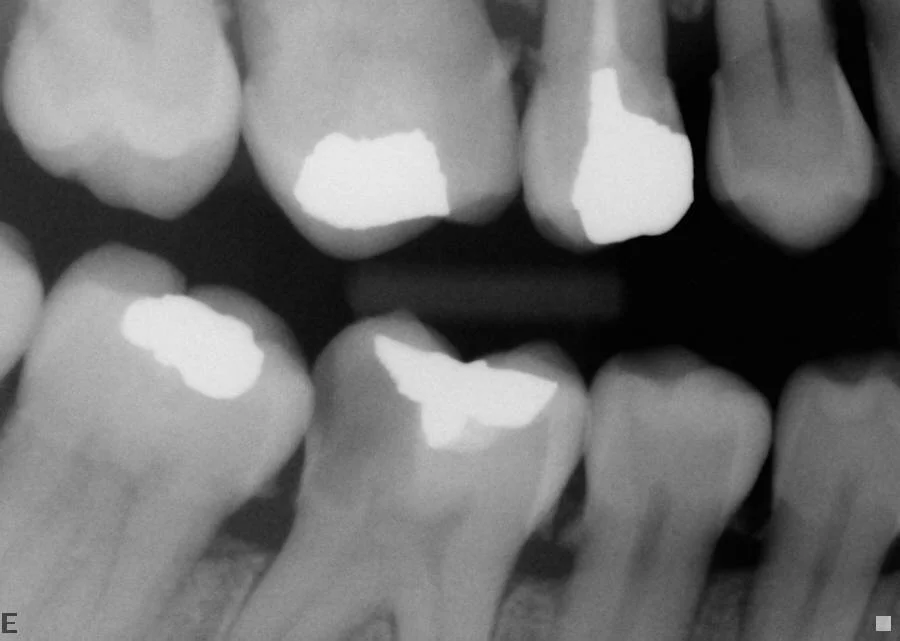

After: Infected lower left teeth